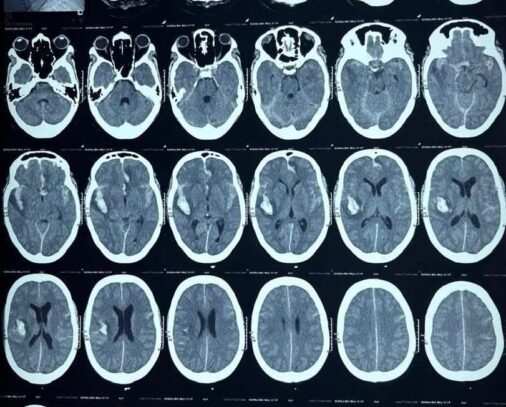

A Traumatic Brain Injury (TBI) is an injury to the brain caused by an external physical force, which results in temporary or permanent impairment of...